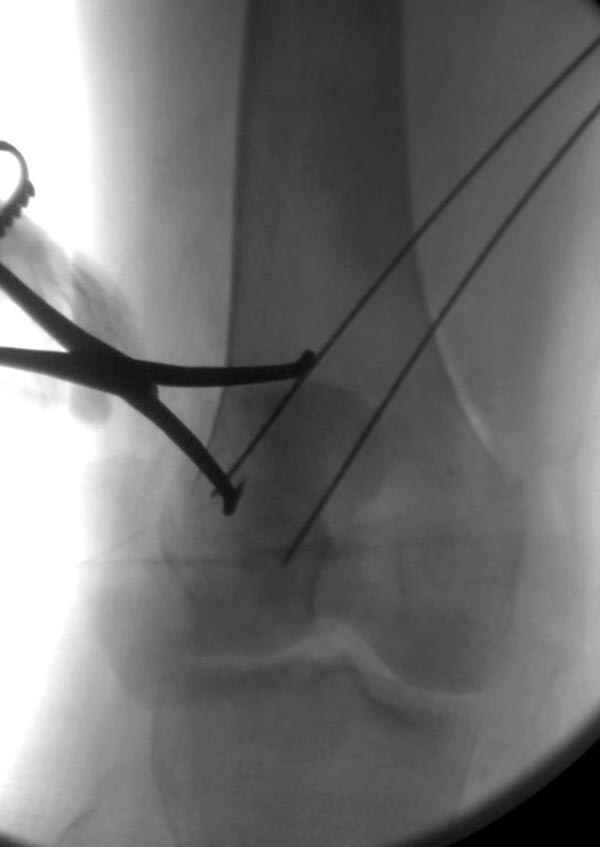

Сегодня досылаю остальные снимки, которые не прошли вчера. Как вчера писал, после фиксации перелома надколенника с дефектом кости и собственной связки, наложили ваккуум и наружный фиксатор. (снимки 4-9)

Внешний фиксатор держим около 6 недель, поэтому был выбран метод фиксации шурупами и еще линия перелома была диагональной, не было нужды в tension band technique, cannulated screws удобнее, провел спицы и по ним шурупы.

Внешний фиксатор снимаем за пару недель до пластики крестообразных связок, мой партнер специалист по спортивной травме, считает оптимально в 6-8 недель, только не могу догадаться, чем будет производить пластику поврежденной собственной связки?